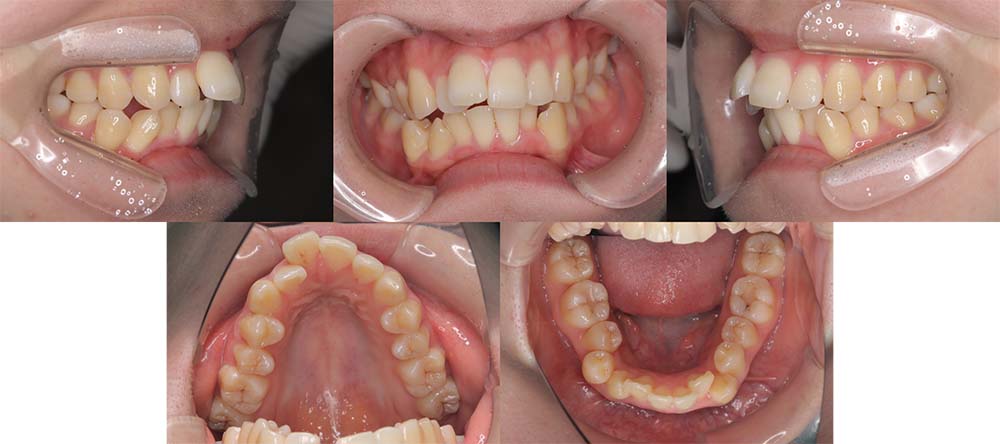

| 症例分類 | 上下顎前突、口唇突出 |

| 診断名 | 口唇突出を伴う上下軽度叢生 |

| 主訴 | 前歯が気になる |

| 年齢 | 15歳8ヶ月 |

| 性別 | 女性 |

| 抜歯部位 | 上下左右の第一小臼歯(4本) |

| 使用装置 | 表側のワイヤー装置 |

| 治療期間 | 1年9ヶ月 |

| 保定装置 | 固定式保定装置、取り外し式保定装置(8時間) |

| 費用 | [検査・診断料] ¥49,500 [基本施術料] ¥792,000 [調整料] ¥4,400/回 [抜歯] ¥5,500/本 [保定装置] ¥55,000(税込) 抜歯や虫歯治療は他院にて費用が別途かかります。(抜歯¥4,000〜10,000/本)

当初は前歯のガタガタを気にされており、上顎の部分治療を希望されました。しかしながら、上顎前歯の叢生のみの改善は可能だが、口唇突出感はなくなり、口が自然に閉じるようにするためには抜歯が必要なことを説明したところ、抜歯して治療することを希望されました。

上下第一小臼歯を抜去して表側のマルチブラケット装置で治療しました。顎間ゴムの協力度が良く予定より早く治療が終了することができました。

口唇突出感をなくし、しっかりと咬合することができました。